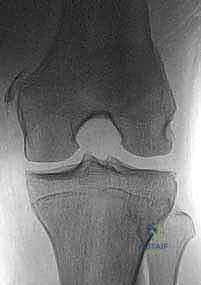

- الأشعة السينية (X-rays): لاستبعاد وجود أي كسور عظمية مصاحبة، مثل كسر قلعي (Avulsion fracture) حيث ينفصل الرباط ساحباً معه قطعة من العظم.